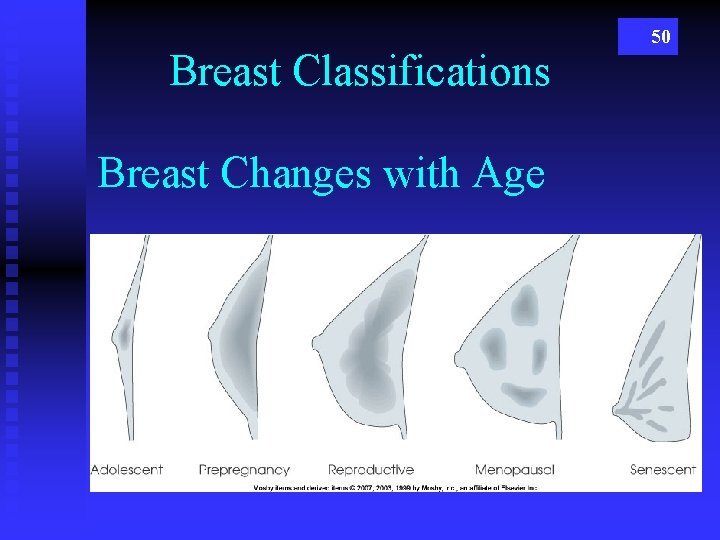

Breast Classifications Breast Changes with Age 50